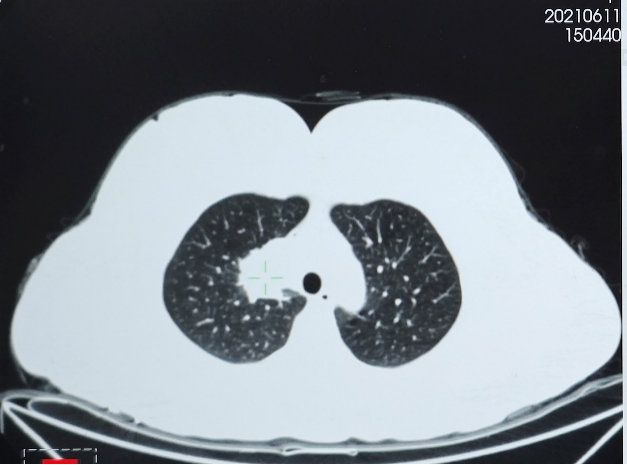

● 胸部CT(2021年6月11日):右肺上叶实性肿块影,大小约34×33mm,考虑肺癌;右肺门及纵隔淋巴结肿大。两肺多发微小结节。

2023年10月24日复查胸部CT,示右肺上叶实性肿块影,大小约37×15mm,与2023年8月25日CT相比病灶增大,评估为靶向治疗耐药导致疾病进展(PD)。